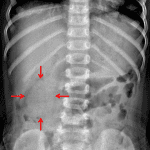

Age: 18 months

Sex: Female

Indication: Abdominal pain

Findings

- Rounded opacity in the right hemiabdomen along the inferior margin of the liver

- Nonobstructive bowel gas pattern

- No evidence of free intraperitoneal air

- No abnormal intraabdominal mass effect or calcification

Diagnosis

- Intussusception

Rounded opacity in the right hemiabdomen along the inferior margin of the liver. Recommend ultrasound to further evaluate for intussusception.

Nonobstructive bowel gas pattern.

No evidence of free intraperitoneal air.

No abnormal intraabdominal mass effect or calcification.